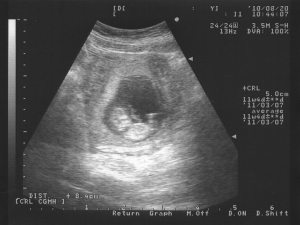

這是我家可愛的baby, 這個大約是三個月的超音波照,真是可愛極了,好像是一個小洋娃娃!不知道是“媽媽的眼睛“情節還是怎樣,好像世界上沒看過更可愛的baby超音波照!頭,身體,腳,臍帶都看得一清二處!

聖經說:未成形的體質,祂都看顧!!你看,上帝就是用看得見baby的眼睛,24小時觀看,照顧baby。